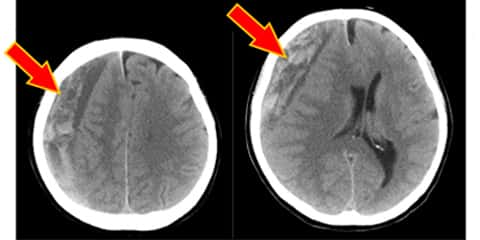

硬膜下血腫を診断するには、医師は通常、コンピューター断層撮影 (CT) または磁気共鳴画像法 ( MRI ) スキャンを使用して、脳の鮮明な画像を取得します。医師は出血の兆候がないかスキャン画像を検査します。

医師が出血を特定した場合、出血の原因を特定し、問題に対処するための行動計画を作成します。